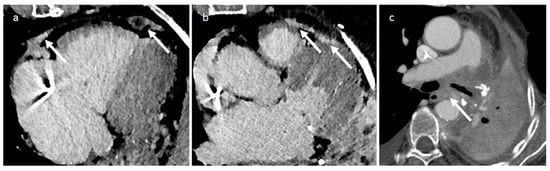

| Erdheim-Chester disease | Adulthood Male to female ratio is 3:1. | RA, AV groove, pericardium | Heart failure, myocardial infarction, tamponade | symmetric osteosclerosis of the metadiaphysis of the lower-extremity bones, RA masses, AV groove infiltration, periarterial infiltration | Pericardial effusion | Right atrium or AV sulcus mass, coronary periaortitis, pericardial thickening and effusion | Strong enhancement |